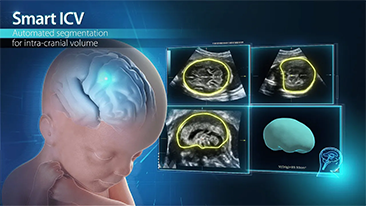

L'optimisation des flux de travail en gynÊcologie et obstÊtrique est indispensable pour traiter les volumes importants de patientes se prÊsentant pour des dÊpistages. Par exemple, les malformations du système nerveux central (SNC) font partie des anomalies congÊnitales les plus frÊquentes. Compte tenu des diffÊrentes conditions dans lesquelles sont rÊalisÊes les Êchographies, par exemple lorsque le f?tus est mal positionnÊ, il est particulièrement difficile de visualiser le plan transcÊrÊbelleux sur les Êchographies 2D. L'automatisation de la dÊtection et de la prise de mesures peut donc grandement amÊliorer l'efficacitÊ de l'imagerie.